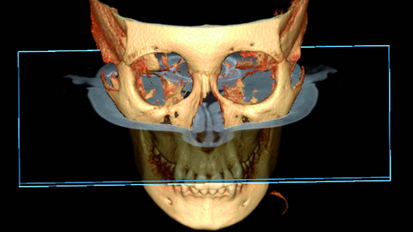

Mastering the implant digital workflow

Whether we like it or not, we are embracing the digital era in our brave new world. Many dental practices are now becoming paper-free—a digital ...